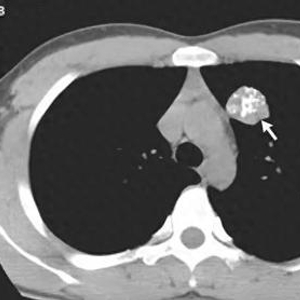

4、冠脉钙化

冠状动脉钙化常发生在有冠状动脉粥样硬化斑块形成的部位,是冠状动脉粥样硬化的重要标志,严重冠脉钙化预示着患者发生心梗的风险较高。